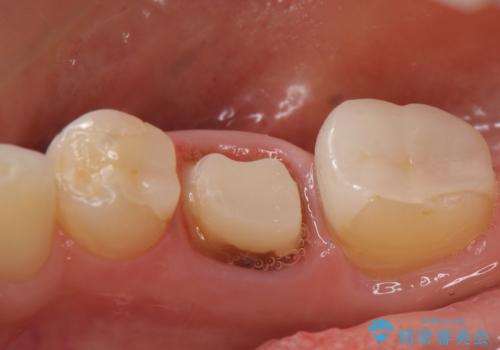

- たまに疼くことがあると他院を受診したところ抜歯を勧められたが、歯を残せないものかと当院にいらっしゃった方の症例です。

診査の結果抜歯の必要性はなさそうだったため再根管治療を行い、その後オールセラミッククラウンによる補綴を行いました。